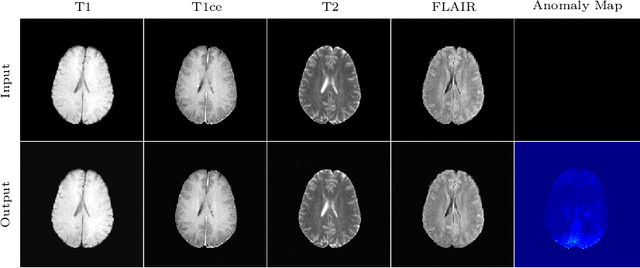

In medical applications, weakly supervised anomaly detection methods are of great interest, as only image-level annotations are required for training. Current anomaly detection methods mainly rely on generative adversarial networks or autoencoder models. Those models are often complicated to train or have difficulties to preserve fine details in the image. We present a novel weakly supervised anomaly detection method based on denoising diffusion implicit models. We combine the deterministic iterative noising and denoising scheme with classifier guidance for image-to-image translation between diseased and healthy subjects. Our method generates very detailed anomaly maps without the need for a complex training procedure. We evaluate our method on the BRATS2020 dataset for brain tumor detection and the CheXpert dataset for detecting pleural effusions.